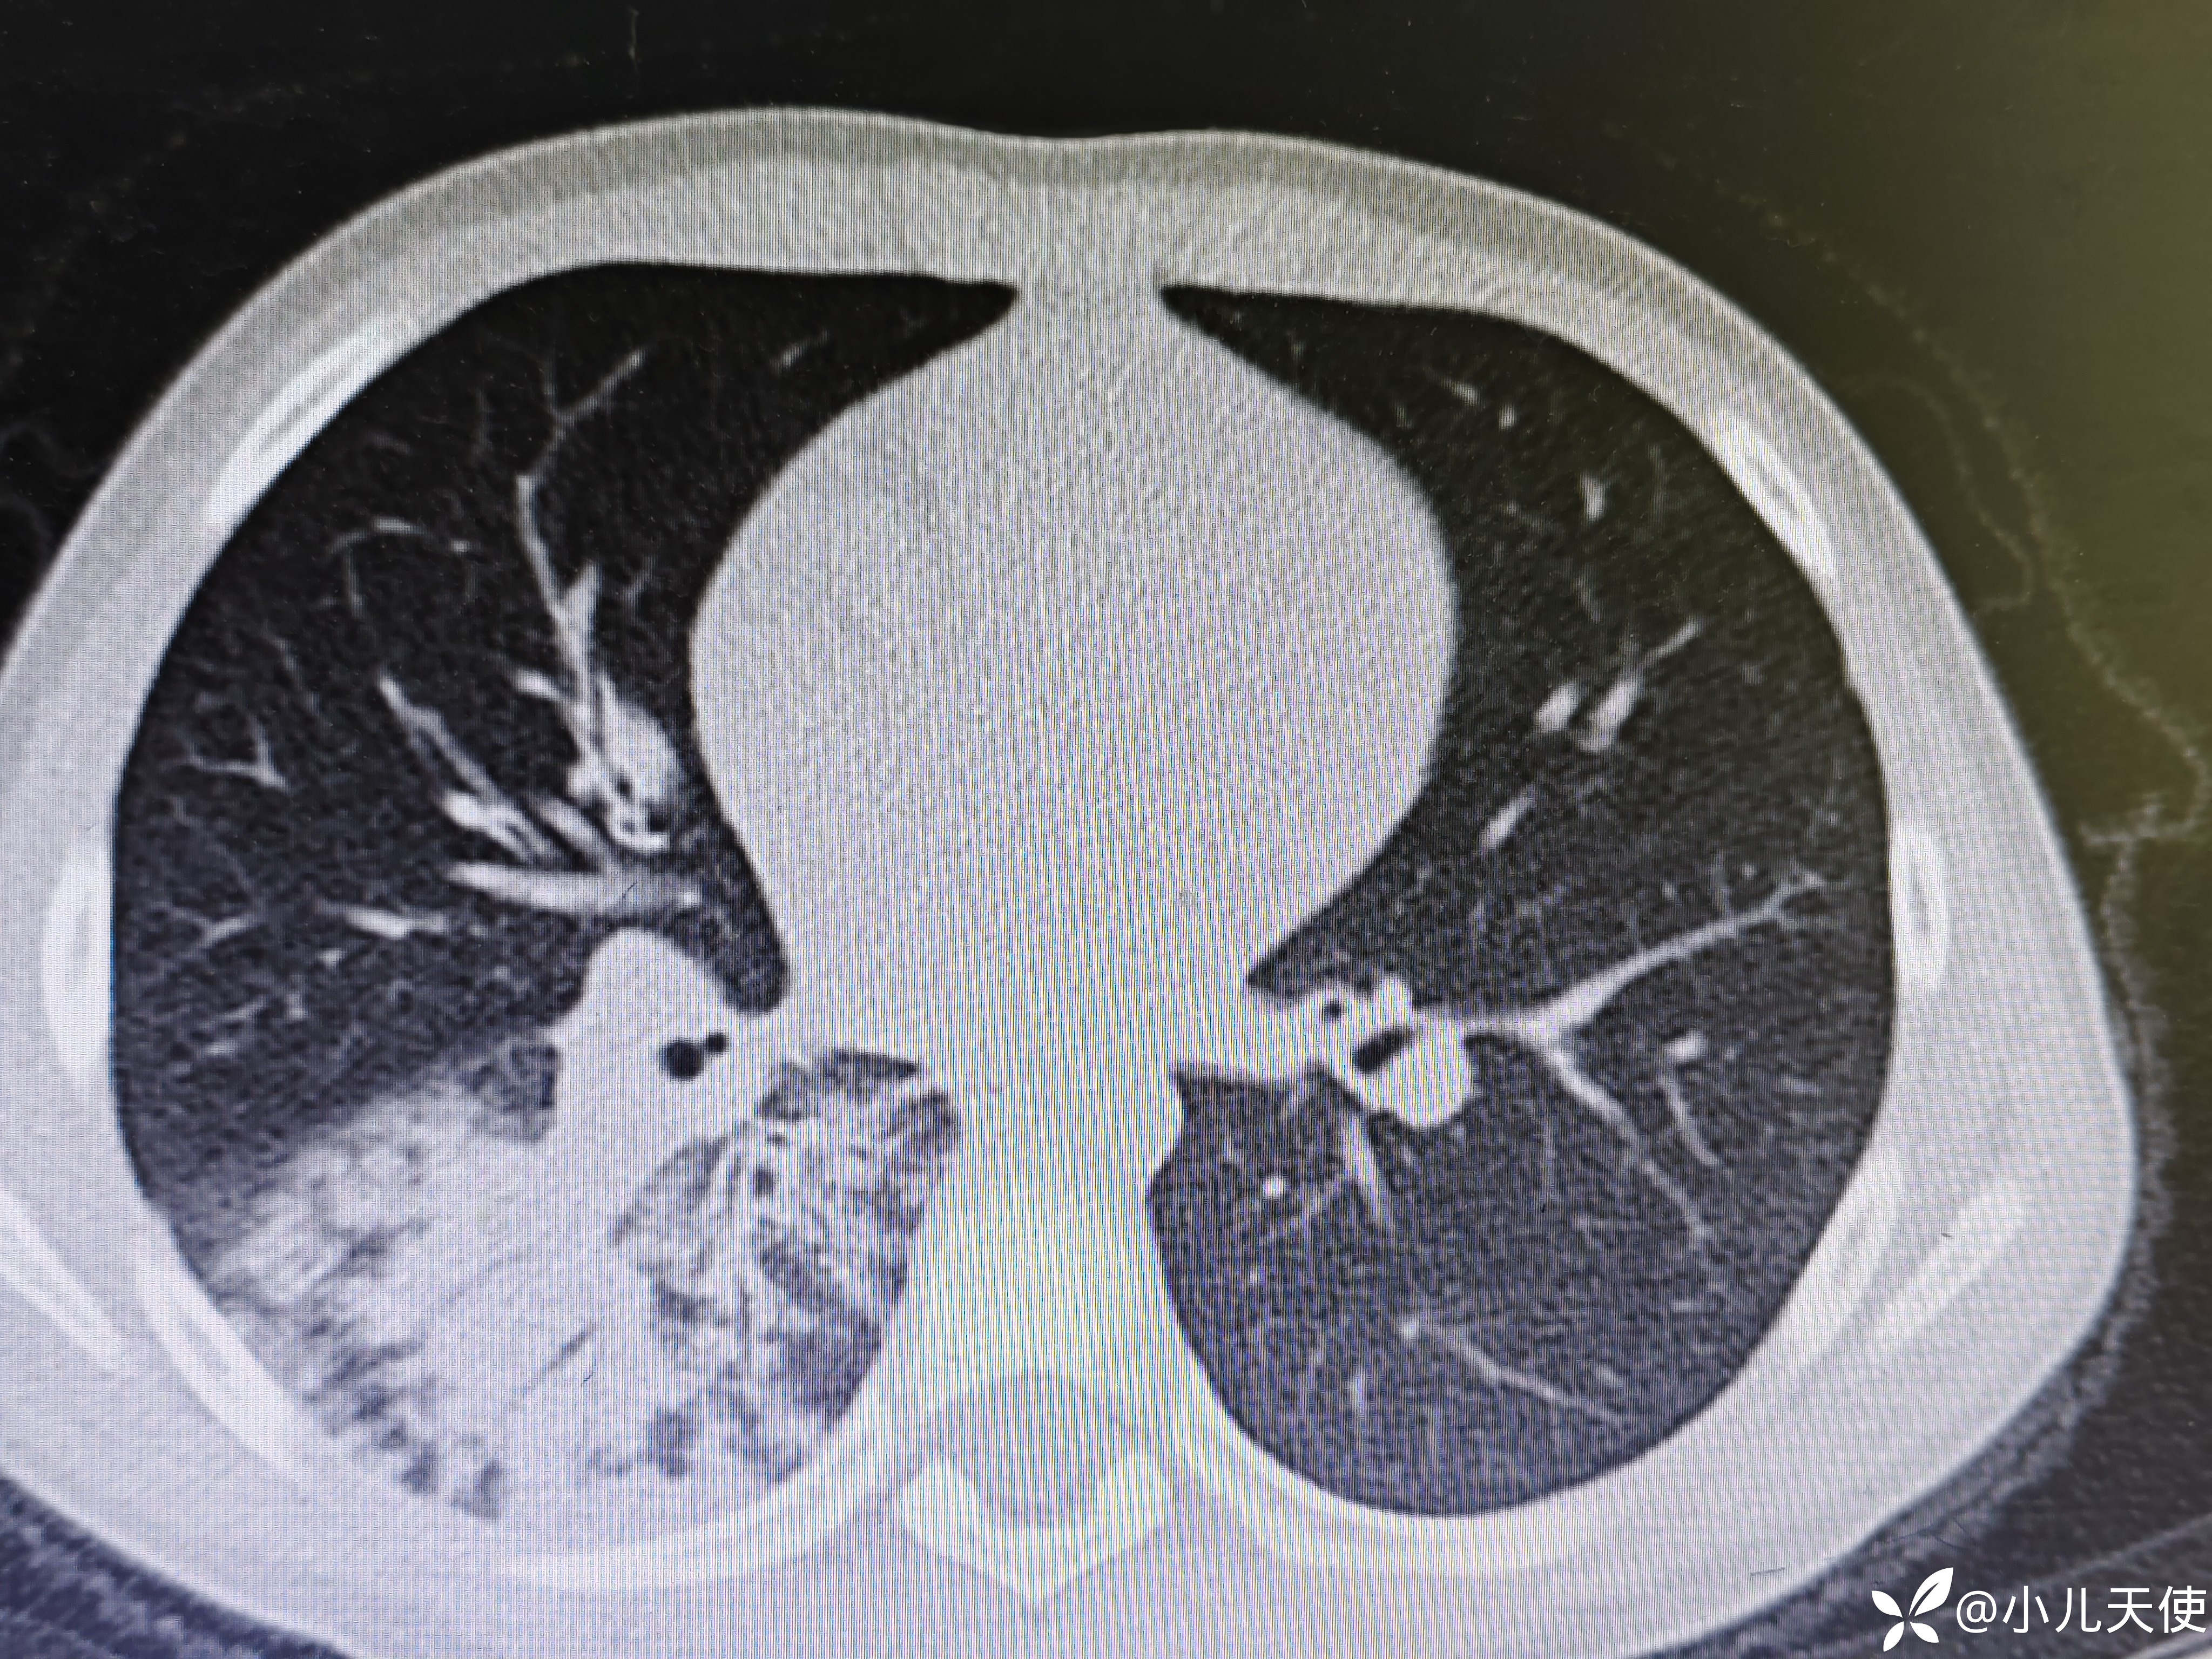

近期6岁女性患儿,发热5天咳嗽4天入院,入院时右肺可闻及明显湿性啰音,支原体衣原体IgM抗体阴性,甲流乙流抗原阴性,腺病毒、结核抗体阴性。血象,CRP、PCT均不高,ESR28,CT见上图。经抗感染(头孢,阿奇霉素)、抗炎(甲强2mg/㎏)等治疗一周,体温第二天即稳定,现肺部啰音已无,咳嗽明显好转,复查胸部CT见下图